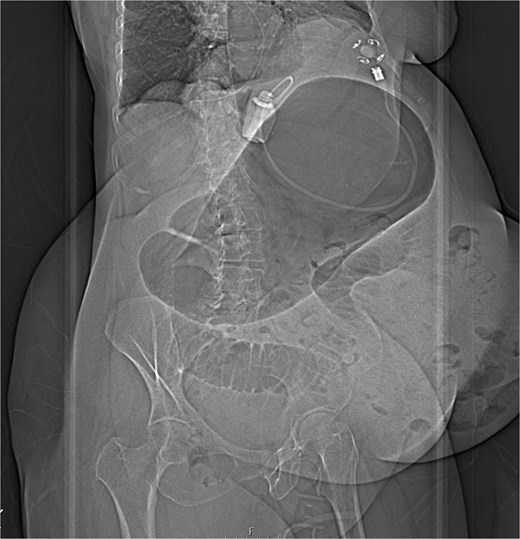

Immediate action involved removing fluid from the gastric band and inserting a nasogastric tube, which was slightly difficult. Only 200 ml of gastric content was drained, and no air was present (indicating that it was not in the stomach). Given the possibility of anatomical pathology or obstruction at the gastroesophageal junction (GEJ), we avoided excessive force when inserting the tube to prevent iatrogenic esophageal perforation. A computed tomography (CT) scan with liquid-soluble contrast media showed that the contrast did not pass beyond the band. The scan also revealed massive gastric dilatation, as well as dilation of the esophagus proximal to the band (Figs 2–4).

CT axial view—contrast media in distal esophagus did not pass to the stomach.

The CT also showed a large ventral hernia in the anterior abdominal wall on the left side, with several entrances and exits for intestinal loops within the hernia. The proximal loops appeared dilated up to 5 cm, with fat stranding and slight fluid between the loops, as well as mild prominence of the mesenteric blood vessels. Distal loops were collapsed, raising suspicion of high-grade obstruction with ischemic bowel involvement (Fig. 5).

CT axial view—obstructed ventral hernia with proximal small bowel loop dilatation.